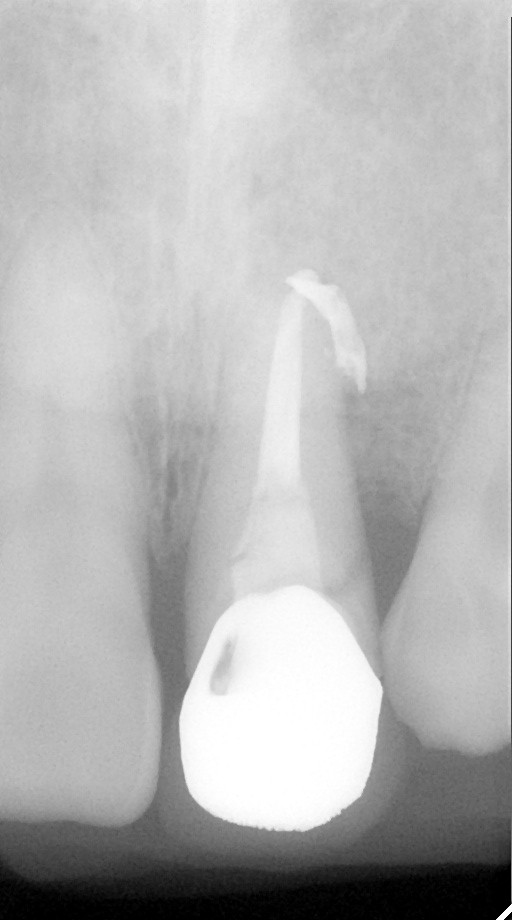

インプラント治療の症例紹介②

Before

After

主訴

前歯の脱落、歯肉の腫れ

治療内容

修復物の脱落時に支台築造のポスト部で歯質を破折。抜歯即時インプラント埋入をおこなったケース。

治療費

473,000 円(税込)

治療期間

8か月

治療回数

12回

想定されたリスク

※経年的な歯肉退縮の恐れ、インプラント周囲炎の恐れがありました。

残存した歯根に感染が少なく、抜歯時即時にインプラント埋入手術を行った。術後〇年経過し安定している状態。